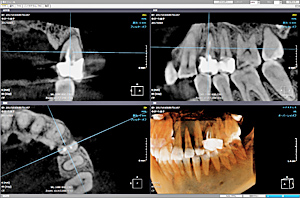

1.顎の検査と、歯の検査

特に、部分入れ歯の場合は、顎の骨の状態(地盤)と、残っている歯の状態(柱)の検査を行い、補修工事や、設計の回避を行います。

- 歯周病の検査、治療

- レントゲン検査、場合によってはCT検査。